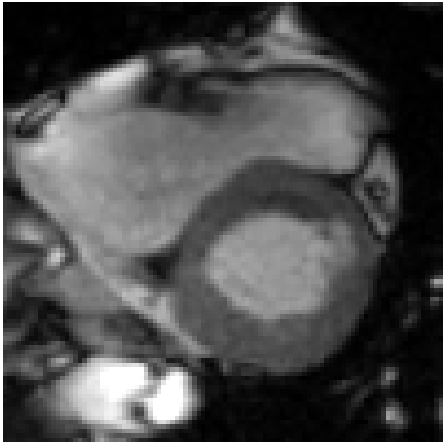

Refer to caption

(a)

(b)

(c)

Figure 4: Qualitative evaluation of reconstruction performance of our method on cardiac cine MRI (ACDC dataset). (a) Original cardiac MRI scan; (b) Its reconstruction and (c) Differences between original (minuend) and corresponding reconstructed (subtrahend) slice. Note that to reconstruct a slice xnsubscript𝑥𝑛x_{n} the mixing coefficient α𝛼\alpha in Equation 1 is set to zero. Blue corresponds to negative and red to positive differences. Image intensities are scaled to a [0,1]01[0,1] range. All difference images use the same color scale [1,1]11[-1,1].

Slice Reconstruction: Results for reconstructed and synthesized slices listed in Table I convey that the proposed approach achieved high reconstruction performance especially in terms of SSIM and PSNR. Figure 4 depicts qualitative results of reconstruction performance for the proposed method on cardiac MRI. The results show that the trained autoencoder can reconstruct high-quality images i.e. input slices. Nevertheless, difference image shown in Figure 4(c) depicts that some high spatial frequency details of the input slice are lacking in the reconstructed slice.